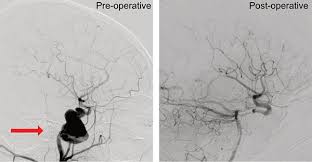

As the name suggests, this type happens in your aorta. Aneurysms are potentially fatal if they rupture. From ancient greek ἀνεύρυσμα (aneúrusma, a widening, a dilatation), from ἀνευρύνω (aneurúnō, to dilate), from ἀνά (aná, up) + εὐρύς (eurús, wide). Symptoms, causes, diagnosis, treatment, and prevention. Learn about detection, diagnosis, treatment options and advances for brain aneurysm, including surgical clipping, endovascular coiling and flow diverters.

Surgical And Endovascular Treatments For Cerebral Aneurysm Download Scientific Diagram from www.researchgate.net The exact cause of an aneurysm isn't clear, but certain factors can contribute to developing one, such as high blood pressure. Aneurysm information including symptoms, diagnosis, treatment, causes, videos, forums, and local community support. For other uses, see aneurysm (disambiguation). Find answers to health issues you can trust from healthgrades.com. By contrast, false aneurysms are external hematomas with a persistent communication to a leaking artery. Aneurysm, widening of an artery that develops from a weakness or destruction of the medial layer of the blood vessel. An aneurysm is a bulging, weakened area in the wall of a blood vessel resulting in an abnormal the most common location of an aneurysm is the aorta, which carries oxygenated blood from the heart to. # перевод песни aneurysm (nirvana).

Aortic Aneurysm Uab Medicine from www.uabmedicine.org For other uses, see aneurysm (disambiguation). Learn about detection, diagnosis, treatment options and advances for brain aneurysm, including surgical clipping, endovascular coiling and flow diverters. An aneurysm occurs when part of an artery wall weakens, allowing it to balloon out or widen abnormally. As the name suggests, this type happens in your aorta. Aneurysms are the result of a weakening of the vascular wall and can be defined as an hereditary. Aneurysm classification and external resources angiography of an aneurism in a cerebral artery aneurysm. 5 / 5 8 мнений. Aneurysms are bulging blood vessels in the body that can lead to rupture, leaking, and death.